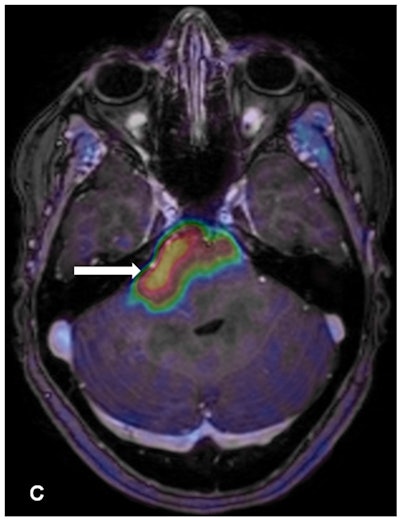

This retrospective study was conducted at University Hospital Zurich and included 12 male and four female patients (mean age, 32 years; range, 16-51 years) who underwent FET-PET between 2010 and 2016. Dynamic PET images were acquired 20 minutes after injection of FET (dose, 135 MBq).

All patients had stable disease at the time of their scans. The researchers also recorded maximum standardized uptake values (SUVmax), tumor-to-brain ratios, and the time activity curve of FET-PET. Progression-free survival was determined based on a mean period of 481 days.

For tumor grades, the researchers had biopsy results for nine of the 16 patients that confirmed the presence of gliomas based on histology. MR morphology was available for the other seven patients to differentiate between high- and low-grade gliomas. In all, the researchers were able to confirm nine high-grade gliomas and seven low-grade gliomas.